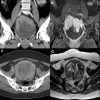

Uterine epithelioid angiosarcoma can have conventional imaging characteristics similar to those of other uterine tumors, such as leiomyoma, leiomyosarcomas or hemangioendothelioma. Uterine epithelioid angiosarcoma exhibiting increased fluorine-18 fluorodeoxyglucose (F-18 FDG) activity can be misdiagnosed. A 61-year-old woman who was diagnosed with uterine epithelioid angiosarcoma underwent F-18 FDG positron emission tomography/computed tomography (PET/CT) as a part of the pretreatment work up for surgery. F-18 FDG PET/CT showed an intense F-18 FDG uptake in the uterus in addition to increased F-18 FDG uptake at the paraaortic and aortocaval lymph nodes. To our knowledge, this is the first case report of intense F-18 FDG uptake in uterine epithelioid angiosarcoma in Korea.